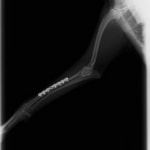

トイプードル 右遠位橈尺骨短斜骨折のALPSによる内固定

Locking Compression Plate

LCPは、スクリュー(ネジ)とプレート(金属の板)をロックする特殊な構造により骨折部位を固定する新しい世代のプレートシステムです。ひとつのホールでロッキングスクリューとスタンダードスクリューの使用を選択できるユニークな構造をしているため、骨折断端間の圧迫を目的とした従来型プレート固定法に加え、高い角度安定性を有するロッキングスクリューを用いた固定法の選択が可能です。従来のプレートシステムでは困難だった部分の骨折や癒合不全の症例に高い治療効果をもたらします。